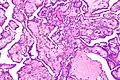

Histology

Cancer cells have distinguishing histological features visible under the microscope.[12][13] The nucleus is often large and irregular, and the cytoplasm may also display abnormalities.[14]

The shape, size, protein composition, and texture of the nucleus are often altered in malignant cells. The nucleus may acquire grooves, folds or indentations, chromatin may aggregate or disperse, and the nucleolus can become enlarged. In normal cells, the nucleus is often round or solid in shape, but in cancer cells the outline is often irregular. Different combinations of abnormalities are characteristic of different cancer types, to the extent that nuclear appearance can be used as a marker in cancer diagnostics and staging.[15]